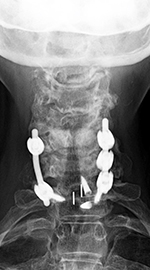

| Cranial tongs (AP view) |

Cranial tongs (lateral view) |

Cervical spine intervertebral disk fusion cage |

Anterior cervical disk fusion (ACDF) and PEEK cage at C5-6 |

| Child with severe intracranial and cervical spine injuries with bilateral cranial stabilization tongs, an endotracheal tube, an oroogastric tube, and a feeding tube entering via the nose.

From Hunter, 2004 |